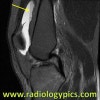

MRI는 전방십자인대 손상의 객관적인 진단 뿐 아니라 손상의 정도와 양상을 평가할 수 있고, 동반 손상을 진단하는데 매우 유용하여 치료방침 결정에 도움을 줄 수 있습니다.

MRI : 혈관절증(Hemarthrosis)